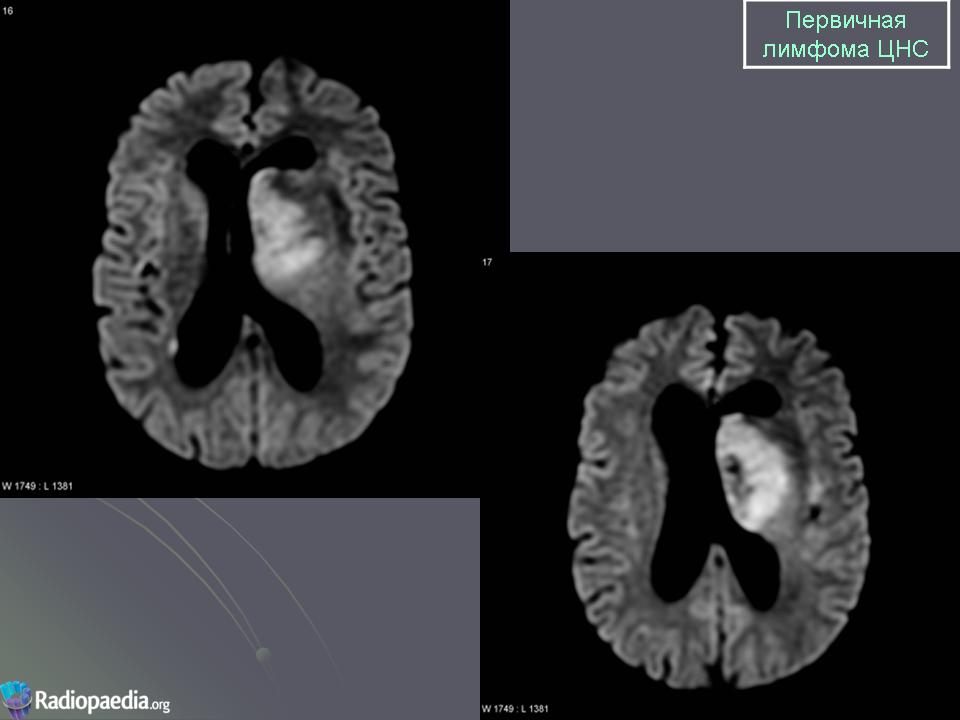

Первичные лимфомы ЦНС. Вс, 22/05/2011 - 21:45 #1 Катенёв Валенти... Не на сайте Был на сайте: 7 лет 5 месяцев назад Зарегистрирован: 22.03.2008 - 22:15 Публикации: 54876 Продолжение.Приложения:

Продолжение.